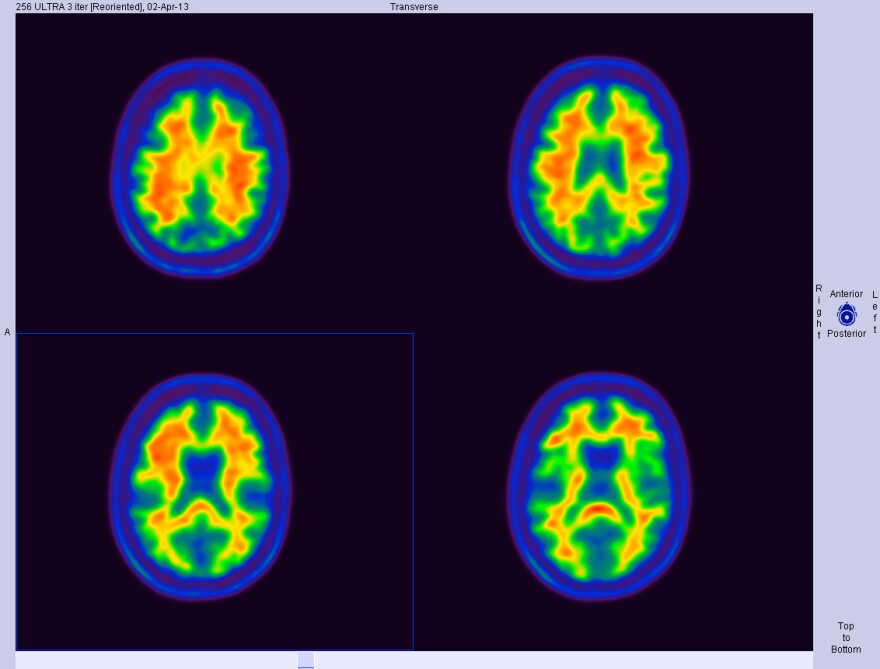

They focused their study on two foot painters who don’t have hands and use their feet for everyday activities like eating and dressing themselves, as well as painting. The two foot painters and 21 other participants who had hands and didn’t use their feet for any dexterous tasks were put in an fMRI scanner while the researchers tapped each of their toes.

The foot painters’ brains reacted in specific areas when their toes were tapped, but non-foot painters brains didn’t. The researchers also noted that in the foot painters, toes were represented in a part of the brain that usually serves to represent hands.